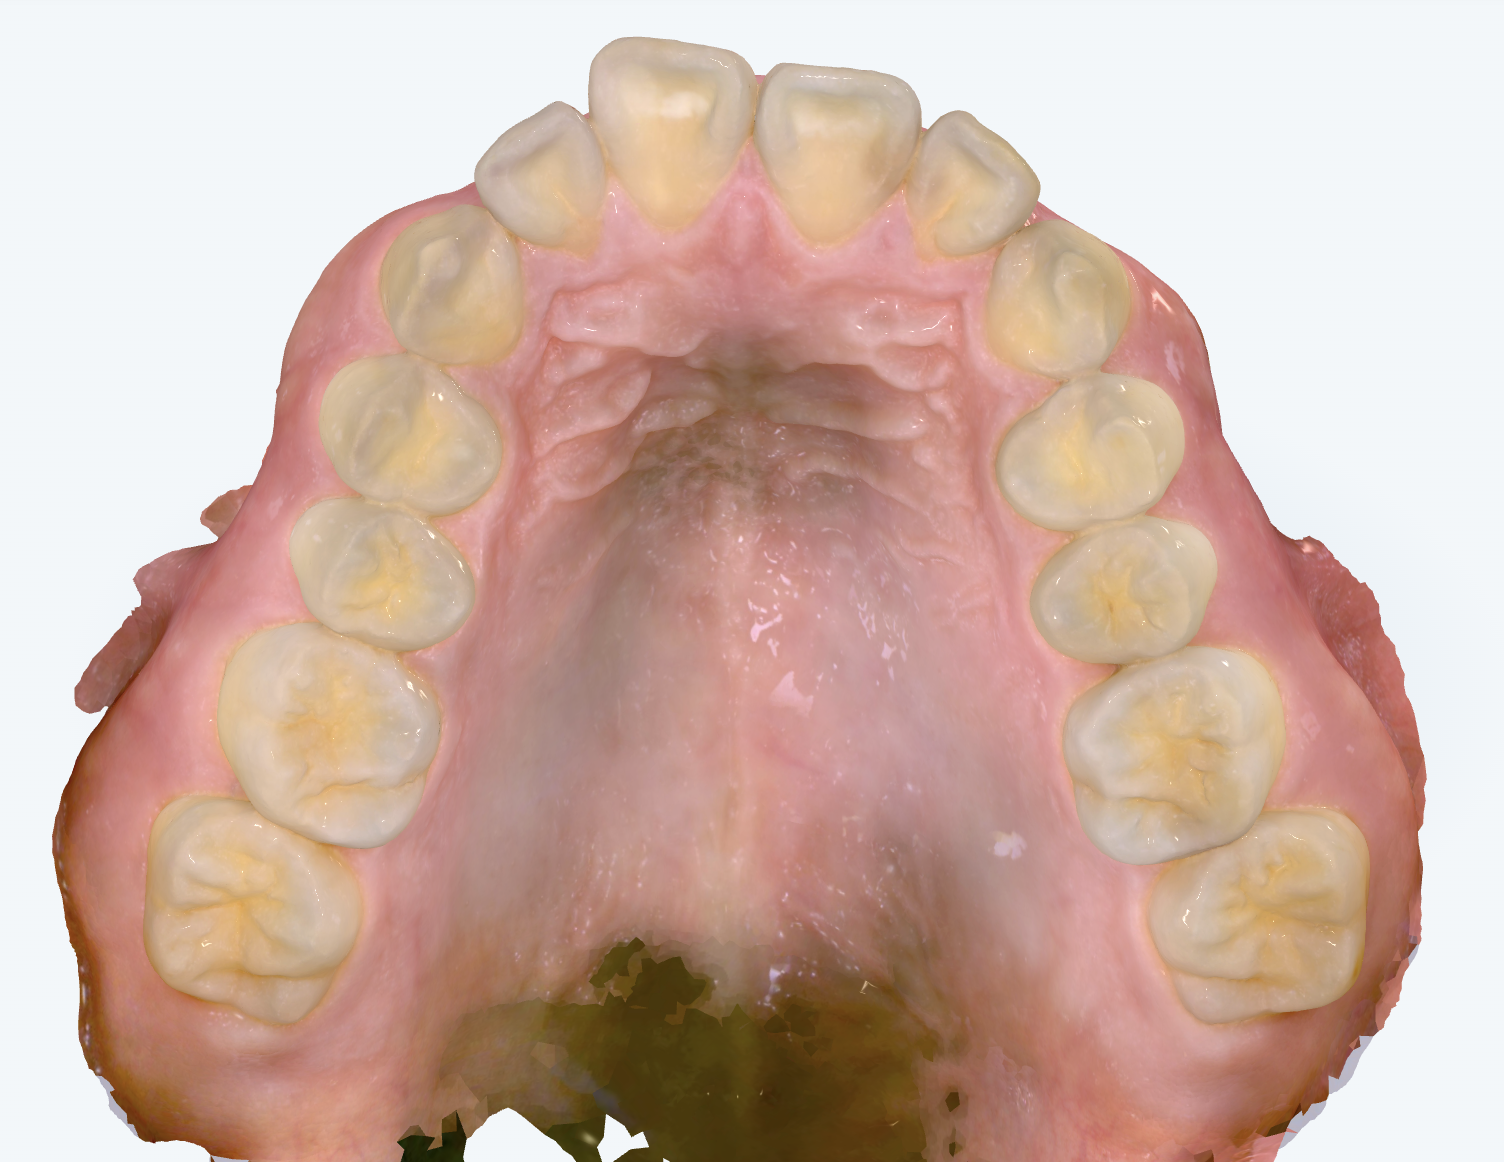

初診時の画像診断

上の前歯が大きく前に傾いていました。奥歯の噛み合わせも出っ歯傾向でした。

上の前歯が前に傾いていることで、口元が出た印象を受けました。リラックスしていると口が開いてしまうとのことでした。